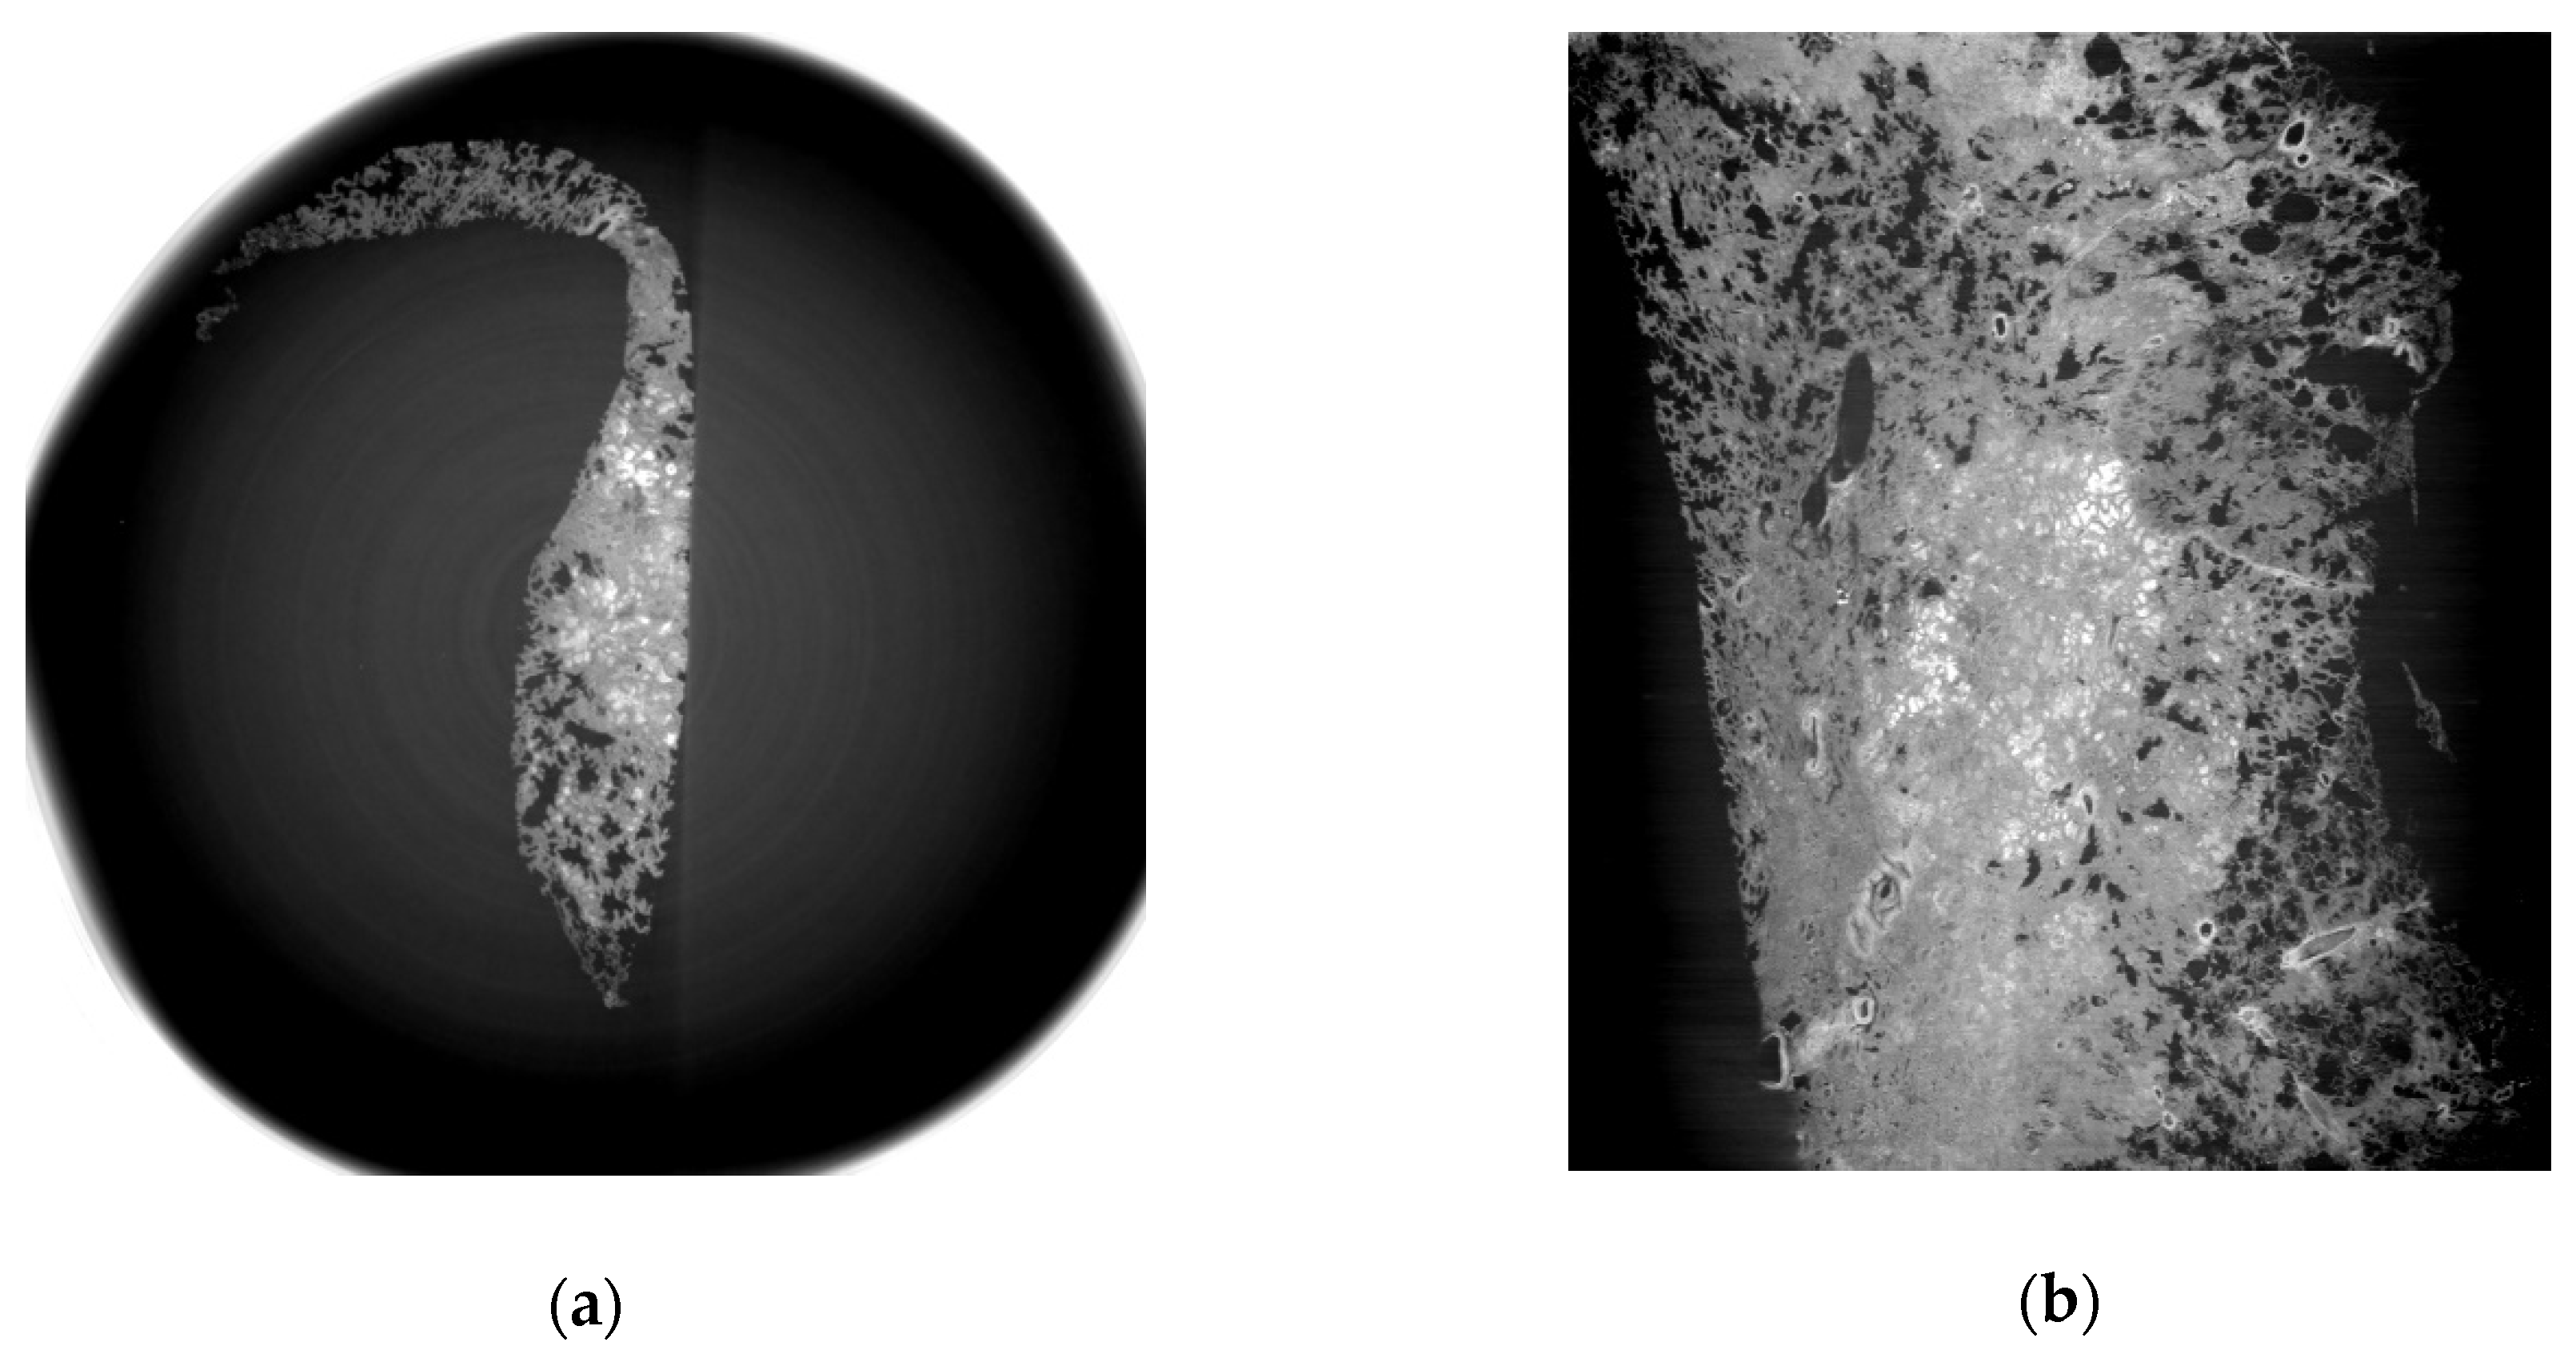

3.1. Refraction-Contrast Synchrotron Tomographic Images of Lung Tissue Including Cancer and 3D Reconstruction

3.2. Comparison with Pathologic Examination